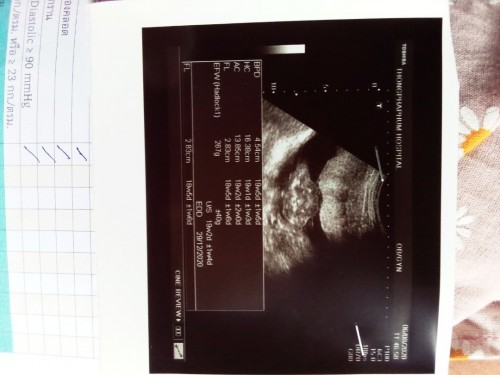

ดูออกไหมคะ

ดูออกกันมั้ยคะ ว่าเพศอะไรดูตรงไหน😊😊

ผู้หญิงไหมคะ

กำลังตั้งครรภ์